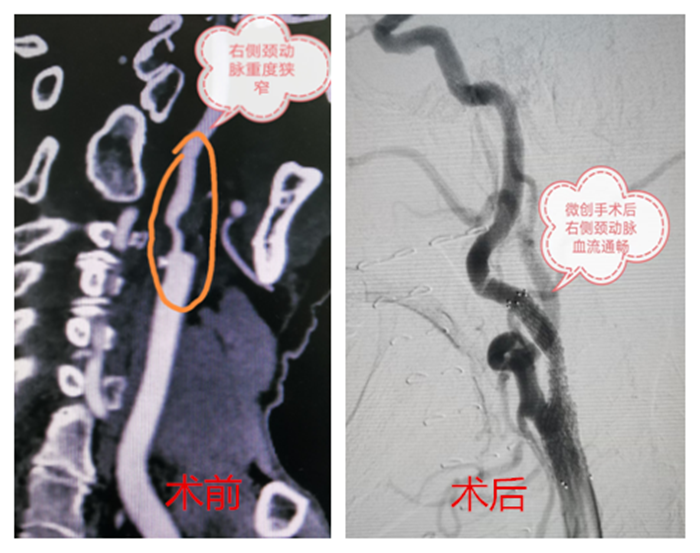

血管外科接診醫(yī)生程國兵仔細(xì)問詢并完善相關(guān)檢查,經(jīng)頸動(dòng)脈CT血管成像提示:右頸內(nèi)動(dòng)脈起始段少量混合斑,管腔中重度狹窄。頭顱磁共振提示:右側(cè)急性腦梗。

在科主任陸煒的帶領(lǐng)下,血管外科診療團(tuán)隊(duì)為祝老先生行“超選擇性右頸動(dòng)脈造影+支架植入球囊擴(kuò)張術(shù)”。在非插管全麻下,穿刺右股動(dòng)脈,置入動(dòng)脈鞘,導(dǎo)絲通過動(dòng)脈鞘進(jìn)入右頸總動(dòng)脈,在右頸動(dòng)脈狹窄段遠(yuǎn)3厘米處放置保護(hù)傘導(dǎo)絲,沿著導(dǎo)絲放置球囊,用球囊壓力泵擴(kuò)張狹窄段,退出球囊后,在狹窄段成功置入支架。短短一個(gè)小時(shí),手術(shù)順利完成。

“太感謝你們了,老爺子‘任督二脈’打通,人都精神多了……”術(shù)后第二天,祝老先生就表示頭已經(jīng)不暈了,家屬深表感謝。